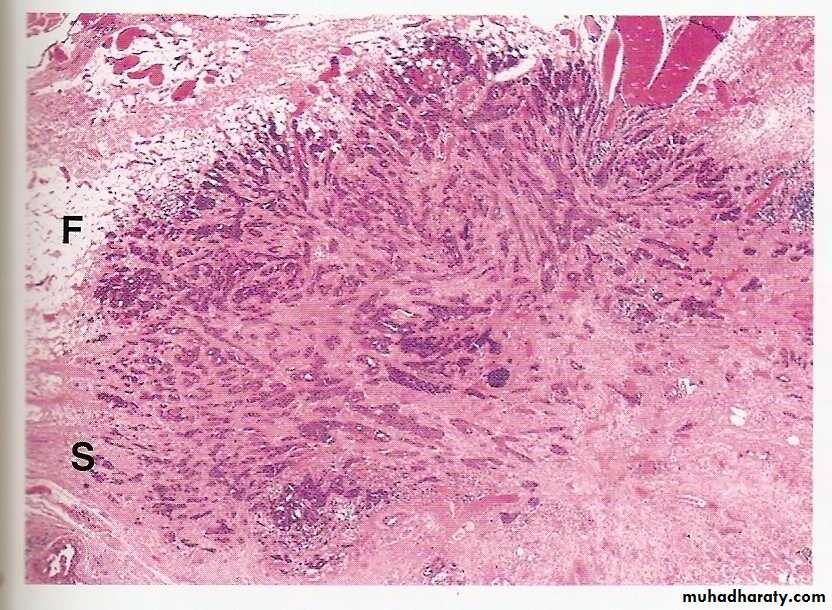

LOCAL INVASION

Most benign tumors grow as cohesive expansile masses that develop a rim of condensed connective tissue or “capsule” at the periphery . They don’t penetrate the capsule or the surrounding normal tissues. The line of cleavage between the capsule and the surrounding normal tissues facilitates surgical enucleation.

Malignant tumors are invasive (infiltrative), they invade and destroy normal surrounding tissues. They usually lack a well-defined capsule or line of cleavage, thus, their enucleation is impossible, and their surgical removal requires removal of a considerable margin of healthy apparently uninvolved tissue.